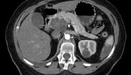

Белок BAP1 подавляет опухоли почек, глаз, желчных протоков и мезотелиомы

BAP1 кодирует ключевой фермент, который взаимодействует с другими ферментами и клеточными компонентами для регулирования генов, что приводит к подавлению опухолей.